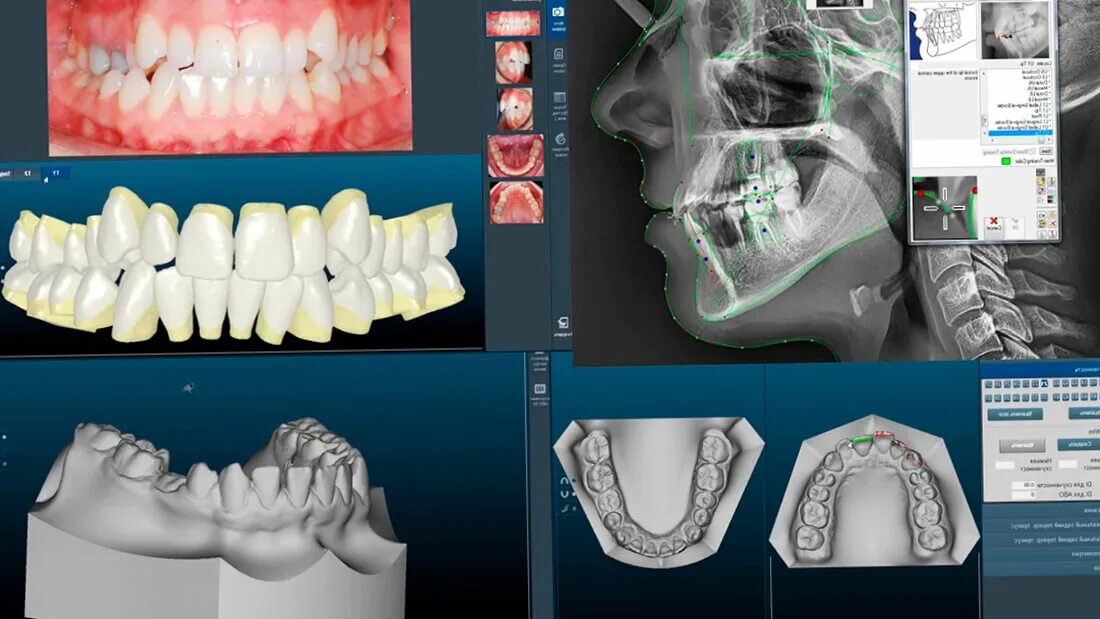

Ошибки кт